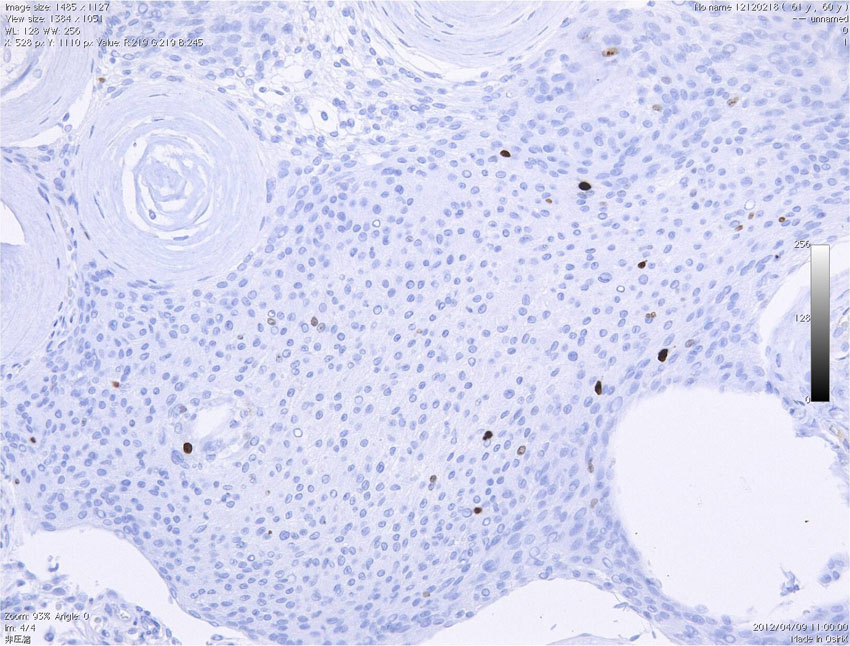

高齢者の後頭窩 (ptrous ridge) にみられた大きな髄膜腫でした。meningiomaと考えられますが、whorl patternやmeningothelial featureなど特徴的なpatternが見られずpattern lessと見做されます。さらに、腫大しchromatinに富む核が見られ、異型細胞と考えられます。

EMAが陽性となることでmeningiomaが示唆されます(左:EMA染色 x200x)。腫瘍の一部でcollagen fiberの多い組織に移行し、核の消失を伴う壊死性変化を示す部位が見られます。

腫瘍の周辺部にonion bulb構造 (→)が見られ、meningiomaの診断が妥当です(左)。細胞核の異型性がありMIB-1 indexが10%と高値であり(右)、atypical meningiomaです。